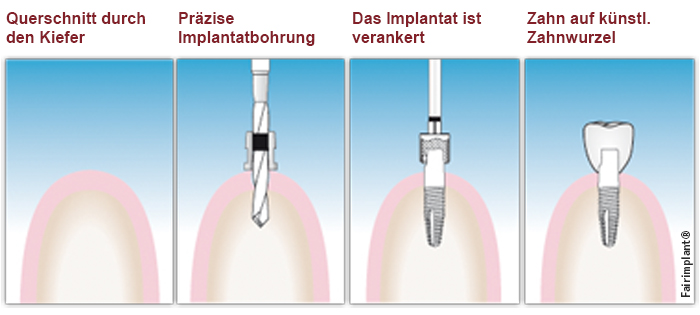

Implantate sind eine solide Basis für hochwertigen Zahnersatz. Wie eine künstliche Zahnwurzel werden die Titanschrauben im Kieferknochen verankert und dann durch den passenden Zahnersatz ergänzt. Von einzelnen Kronen in einer Zahnlücke über Brücken beim Ersatz mehrerer Zähne bis hin zur Komplettsanierung ist alles möglich. Gegenüber dem herkömmlichen Zahnersatz haben die gut verträglichen Titan-Implantate zahlreiche Vorteile: Implantate verwachsen mit dem Kieferknochen und sind dadurch genauso belastbar wie gesunde, natürliche Zähne. Bei herkömmlichen Brücken müssen gesunde Nachbarzähne beschliffen werden. Implantate übernehmen diese Pfeiler-Funktion und schonen so die umliegenden Zähne. Die implantierten Titanstifte fühlen sich nach einer Weile völlig natürlich an. Ein Fremdkörpergefühl wie bei Prothesen entfällt. Durch Nichtbelastung bei Zahnlücken oder ständigen Prothesendruck baut sich mit der Zeit der Kieferknochen ab und der Mund sieht eingefallen aus. Implantate erhalten den für ein jugendliches Aussehen so wichtigen Kieferknochen und tragen damit wesentlich zu einem ästhetischen Gesamteindruck bei. Implantate sind ein Segen für Träger nicht saugender Totalprothesen. Schon zwei Implantate stabilisieren Ihre Prothese so, dass Sie im Alltag ein hohes Maß an Sicherheit gewinnen. Zweiteilige und einteilige Implantate Einteilige Implantate bestehen aus nur einer Komponente. Der für den Zahnersatz nötige Aufbau ist dabei in die Implantatschraube integriert. Nach dem Einbringen ragt der Implantataufbau, beispielsweise ein Pfosten für eine aufzusetzende Krone, schon nach dem ersten Eingriff aus dem Zahnfleisch heraus. Eine Freilegungsoperation ist hier nicht erforderlich. Stimmen die knöchernen Voraussetzungen können in der Regel einteilige Implantate mit der minimalinvasiven Methode der Implantation eingesetzt werden, wobei nur ein kleiner operativer Eingriff unter maximaler Schonung benachbarter Bereiche vorgenommen wird. Aufgrund der schnellen minimalinvasiven Behandlung, den einfacheren Behandlungsabläufen, sowie der geringeren Kosten sind einteilige Implantate eine attraktive Variante zu den herkömmlichen zweiteiligen Implantatsystemen. Wir beraten Sie gerne, ob und welche Art der Implantate bei Ihnen ratsam sind und wie eine Versorgung genau aussehen kann. Dr. Jürgen Wenzel ist zertifizierter Implantologe und Mitglied der Deutschen Gesellschaft für Implantologie und damit Ihr kompetenter Ansprechpartner auf diesem Gebiet.